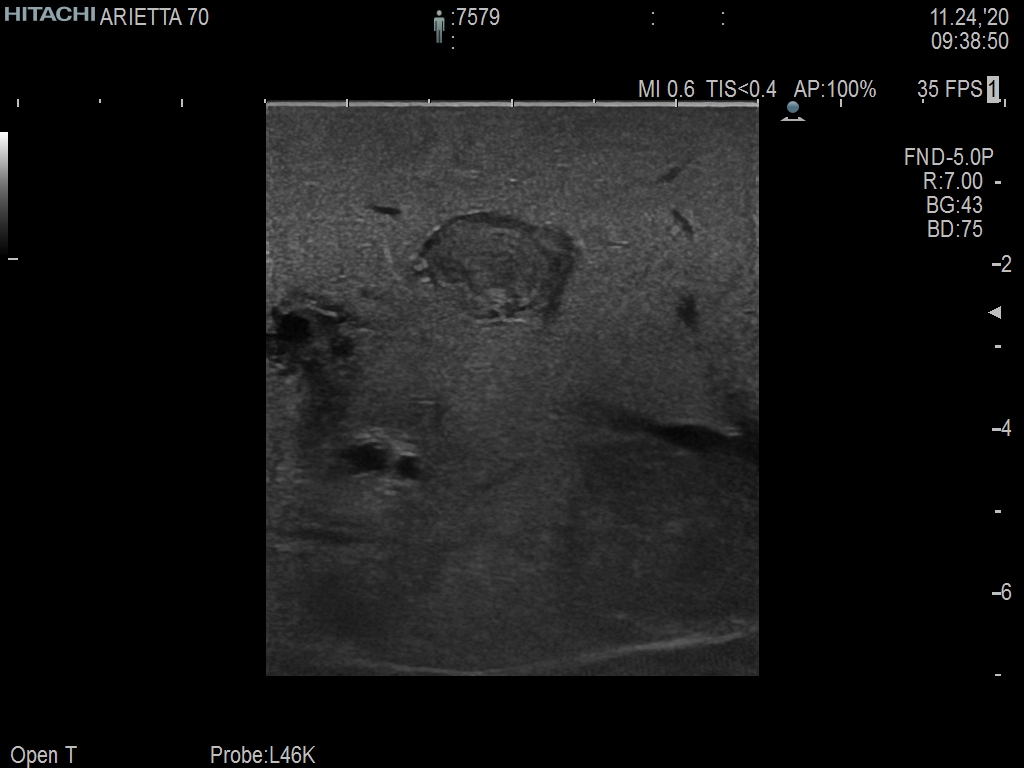

Arietta 70

Recognized for our outstanding image quality, outstanding system reliability and intuitive use of cutting edge technology, Fujifilm Healthcare remains the standard in the field of Surgery.

Learn moreArietta 70

Recognized for our outstanding image quality, outstanding system reliability and intuitive use of cutting edge technology, Fujifilm Healthcare remains the standard in the field of Surgery.

A critical function of robotic ultrasound guidance is tumor margin identification. Fujifilm's family of robotic probes all have the optimum location of the attaching mechanism that allows for full wrist articulation of the probe. The result is an increased confidence that the tumor margins have been completely identified.